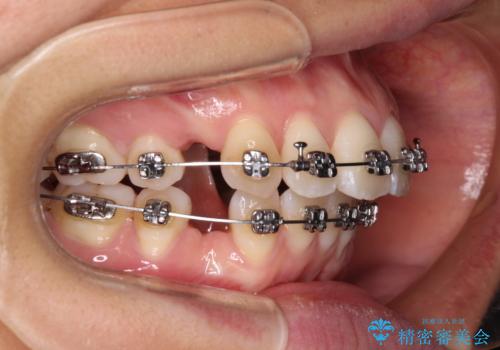

- 矯正装置

- メタルブラケット

非抜歯矯正ではデコボコを解消することでより口元が突出してしまうため、上下左右の小臼歯4本の抜歯を行い、ワイヤー装置による矯正治療を行うこととしました。

もう少し口元の突出感を改善したかったのですが、舌の突出癖が影響し下顎前歯が唇側に押させる仕上がりとなりました。